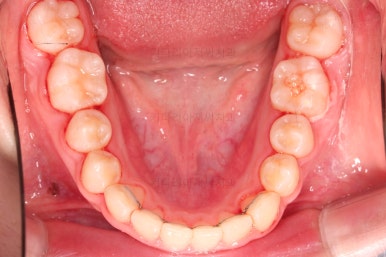

덧니도 개선되었고 가지런한 느낌도 좋네요.

교합도 좋고, 평행하지 않던 느낌도 많이 좋아졌습니다.

전후 사진을 보여드리겠습니다.

많은 부분이 좋아졌고요.

웃을 때 기울어져 보이던 치열의 모습도 좋아졌습니다.